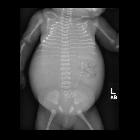

urethral agenesis

Newborn with

oligohydramnios on prenatal US and bilateral large abdominal masses and Potter’s facies on physical exam. Postmortem CXR and AXR shows an extremely distended abdomen due to bilateral abdominal masses resulting in a small thorax. An umbilical catheter fragment is also present.The diagnosis was urethral atresia causing bladder outlet obstruction resulting in bilateral hydroureteronephrosis and subsequent cystic renal dysplasia.